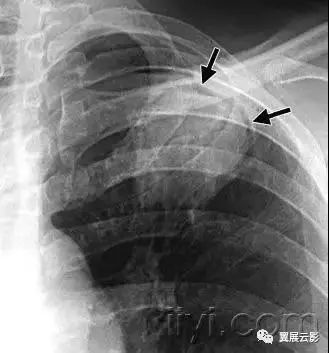

五十六、气胸和张力性气胸

病理:气胸指胸膜腔内出现气体。包括自发性、外伤性、诊断性和张力性气胸。张力性气胸是指胸膜腔内气体积聚,具有一定的压力。正常情况下,以此肺会完全压缩塌陷,而在顺应性减低的肺,可以保持膨胀不全。

平片和CT:在胸片上,可以看到脏层胸膜边,图55,除非气胸量很少,或者胸膜边缘与x线不呈切线位。张力性气胸可以出现明显的纵隔移位和/或一侧膈压低。一些非张力性气胸也可以出现纵隔移位,这是由于病变侧胸膜腔内压力达到大气压,而健侧胸膜腔压力为负造成的。